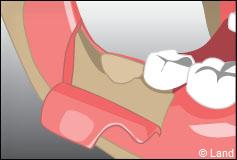

Certaines dents n’arrivent pas à faire leur éruption sur l’arcade correctement, présentent un accès difficile (dents de sagesses), ont des racines divergentes ou très courbées, ou sont considérablement abîmées (carie importante par exemple). Aussi elles restent souvent en partie ou totalement incluses dans l’os. On procède alors à une extraction chirurgicale.

L’intervention commence là aussi par une anesthésie locale, puis le chirurgien-dentiste procède à une incision de la gencive et à un dégagement du tissu osseux autour de la dent.

Parfois cette dernière est sectionnée pour ne pas traumatiser l’os souvent responsable de suites opératoires douloureuses.

La fermeture de la cavité s’effectue souvent à l’aide de points de suture servant à réunir les bords de la gencive.